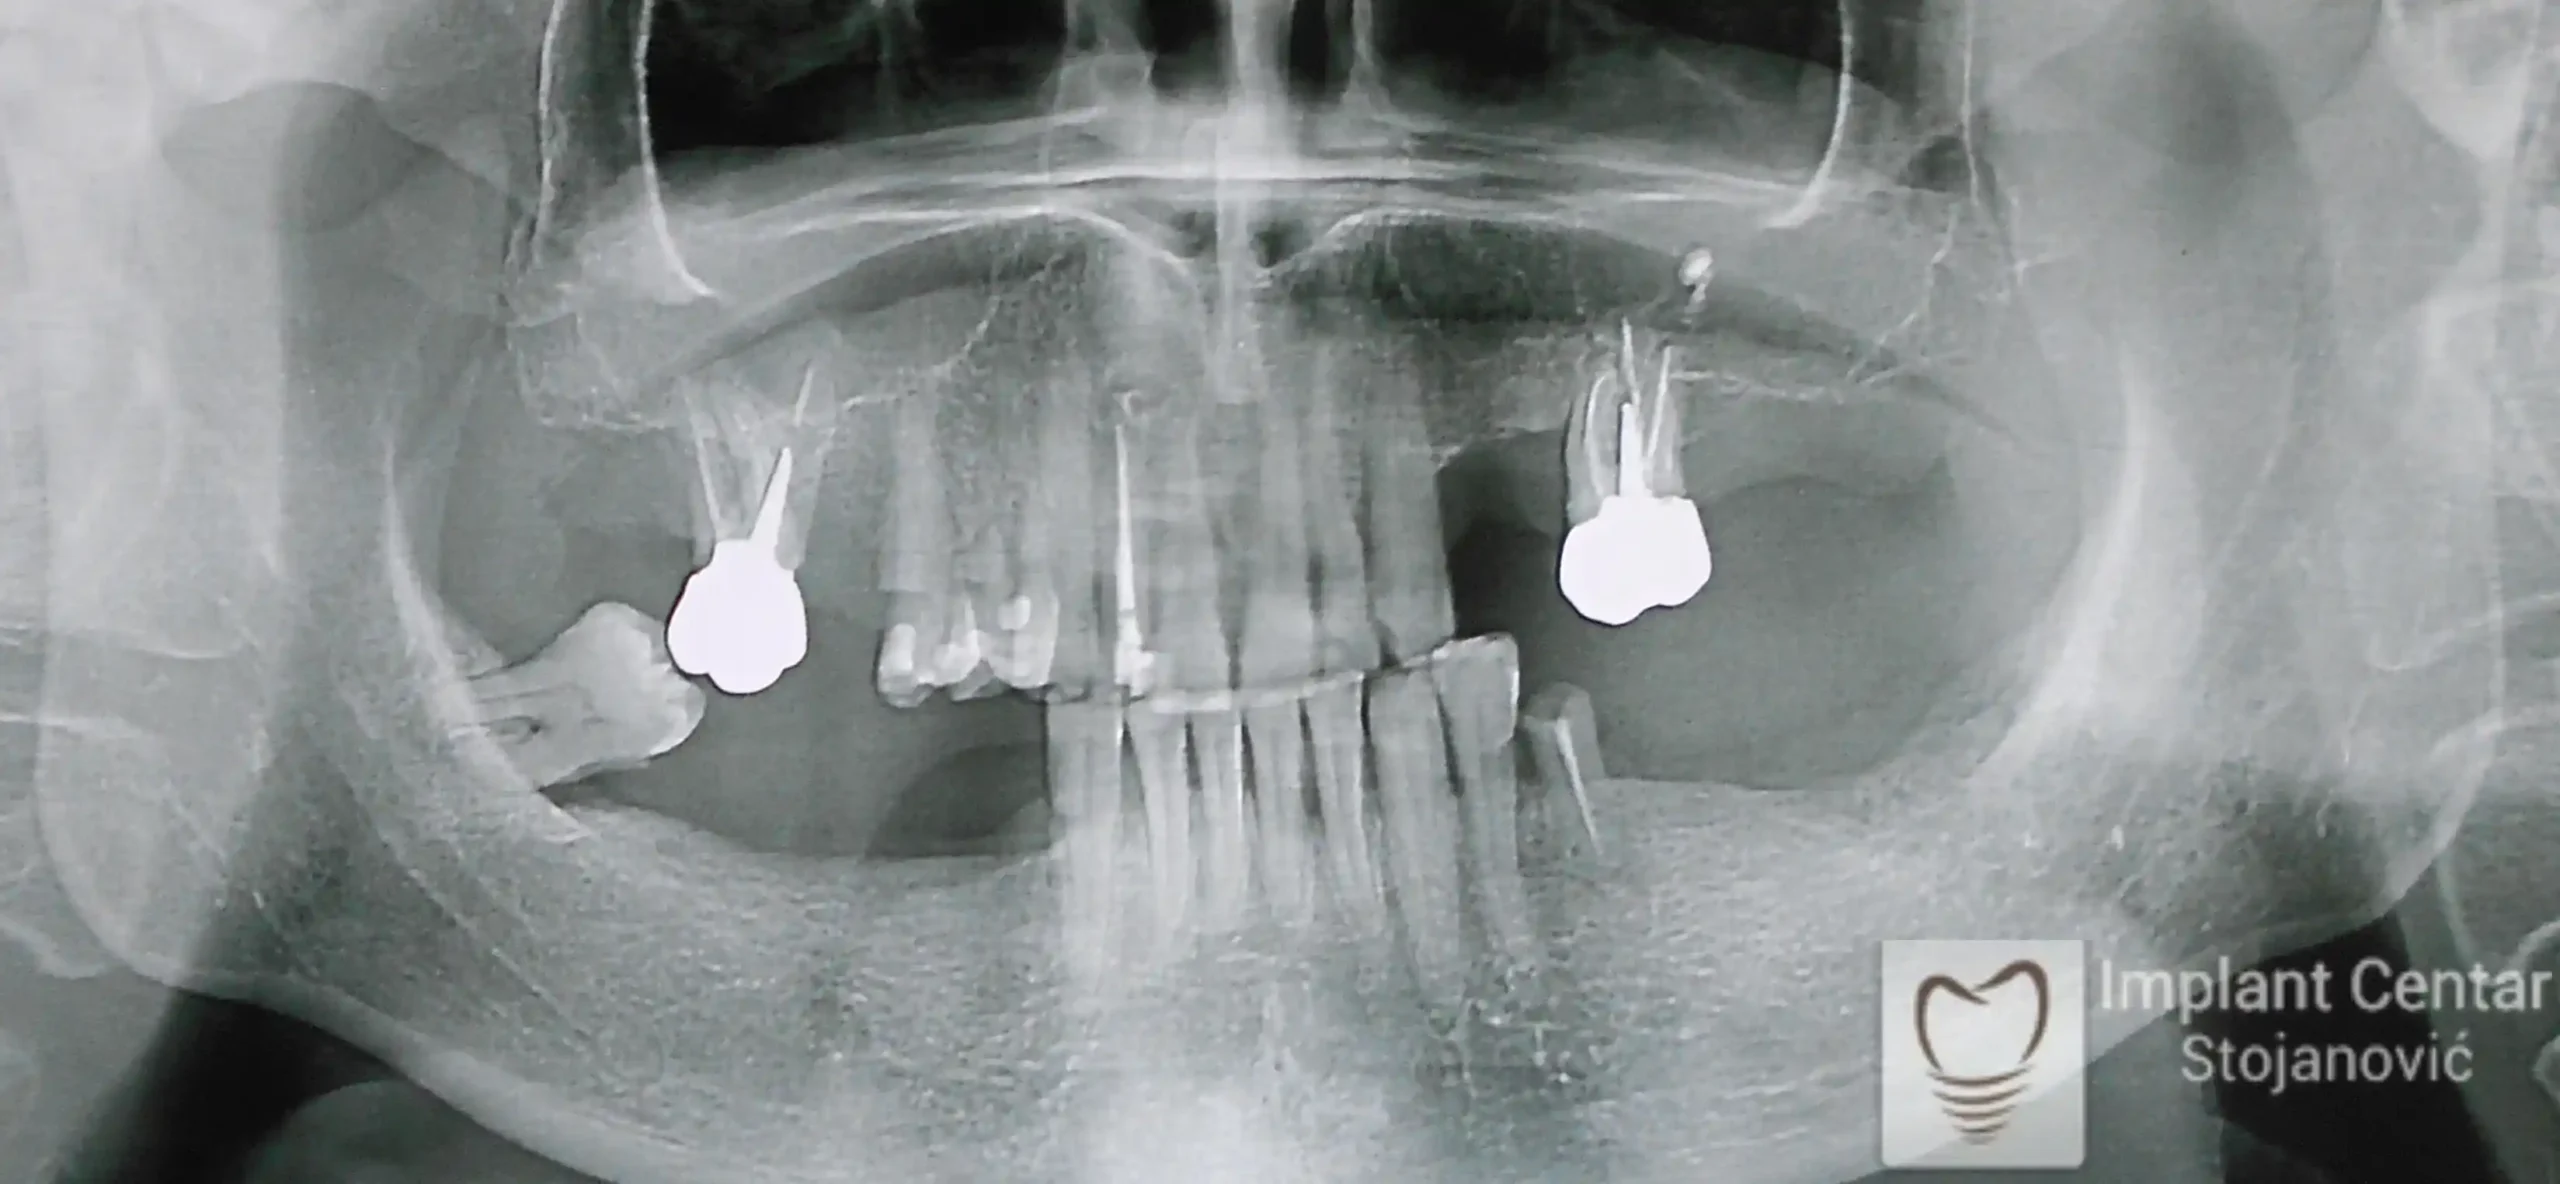

Na slici 1. i slici 2. prikazan je izgled pacijenta pre početka terapije – klinički i rendgenološki.

Na slikama 1 i 2 prikazan je klinički izgled pacijenta pre početka terapije. Nakon detaljnog kliničkog pregleda, analize radioloških snimaka, kao i razgovora sa pacijentom o njegovim željama i očekivanjima, izrađen je sveobuhvatan plan terapije. Terapija je podrazumevala vađenje preostalih zuba, ugradnju dentalnih implantata i izradu fiksnog protetskog rada na implantatima.